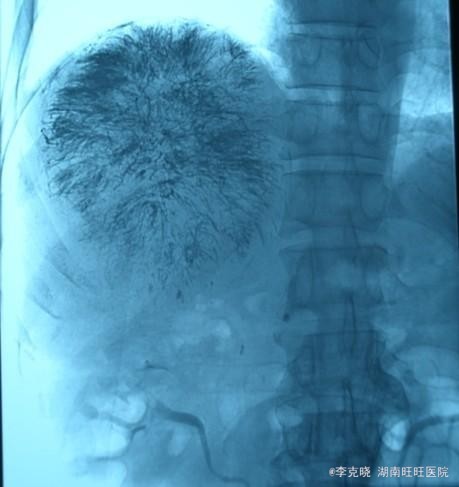

四测正常,皮肤巩膜无黄染,心肺部听诊未闻及杂音。腹平坦,未见胃肠型及蠕动波,无腹壁静脉曲张,全腹柔软,右侧肋缘深压痛,无反跳痛,肝肾无叩痛,肝肺浊音界清晰,肠鸣音正常。四肢活动自如,无水肿。 辅助检查提示:血常规、凝血常规基本正常,谷丙转氨酶278u/l,谷草转氨酶326u/l,AFP大于20000。上腹部CT增强提示:右肝巨大占位,平扫期呈低密度,动脉扫描时强化明显,静脉延迟象呈现低密度,结合病史考虑原发性肝癌可能,建议结合临床。

诊断:原发性肝癌(右肝巨块型)。治疗:考虑到患者的经济状况,结合肿瘤的影像学特点,经与患者充分沟通“以手术治疗为主的肝癌综合治疗思路”,最终患者选择先行TACE治疗。治疗后住院9天复查肝功能,转氨酶有下降趋势时,给予患者出院。一个半月后返院复查,转氨酶稍高,肿瘤内部碘油沉积满意,未见新生血管生成和新生病灶,建议患者继续观察、随访。